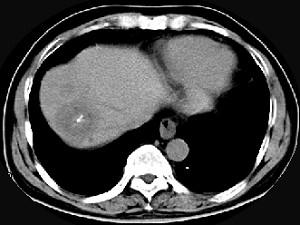

问题 男性,54岁,右上腹部不适,CT检查如图,最可能的诊断是 ( )

选项 A、肝血管瘤伴肝脓肿 B、肝血管瘤伴炎性肉芽肿 C、肝多发血管瘤 D、肝血管瘤伴肝癌 E、肝血管瘤伴转移瘤

答案 C